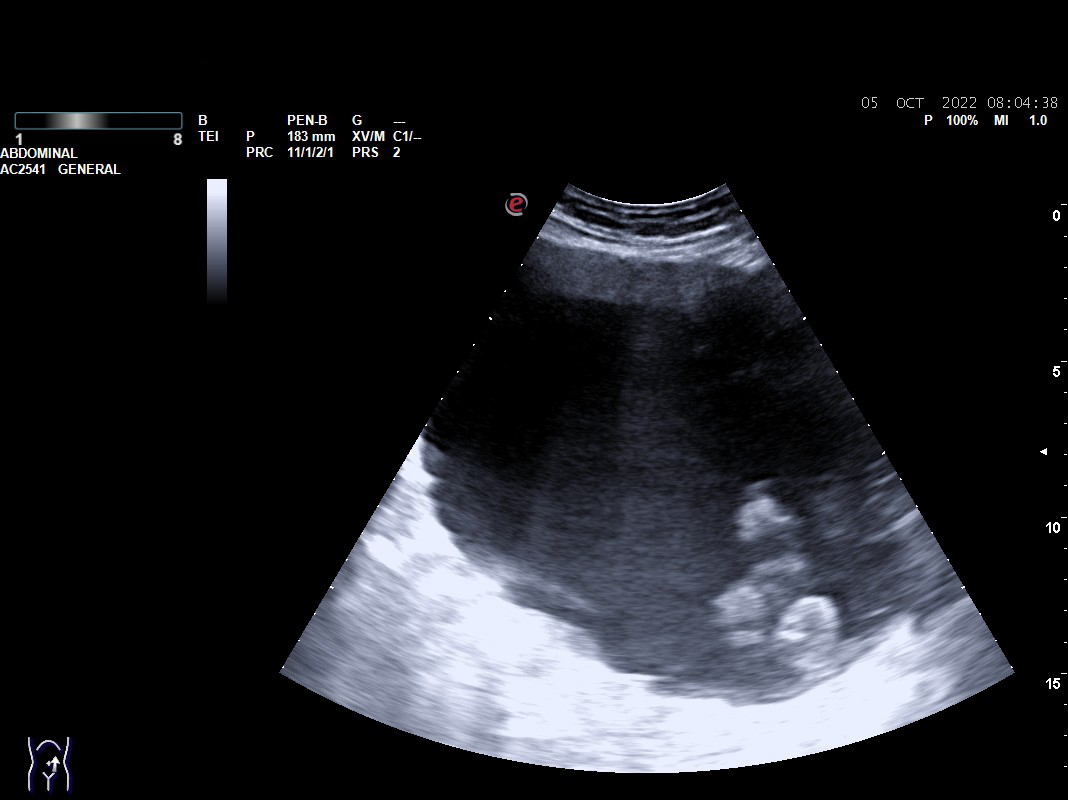

Objetivamos formación quística compleja tabicada de 17 x 10 cm con cámaras en su interior que parece depender de ovario, sin vascularización. Presencia de líquido libre en Douglas.

Con sospecha de formación anexial se deriva a Urgencias de Ginecología para valoración: exploración ginecológica normal y en Eco-Doppler-Transvaginal confirman formación multicameral sonoluscente localizada en zona central de pelvis, suprauterina hasta un través por encima de ombligo, ocupando toda la pelvis de 176 x 107 mm con múltiples cámaras en polo superior derecho. No se visualiza líquido libre en hemiabdomen superior, no impresiona de carcinomatosis  ni de dilatación de pelvis renales. Líquido libre en Douglas moderado. Sin ascitis.